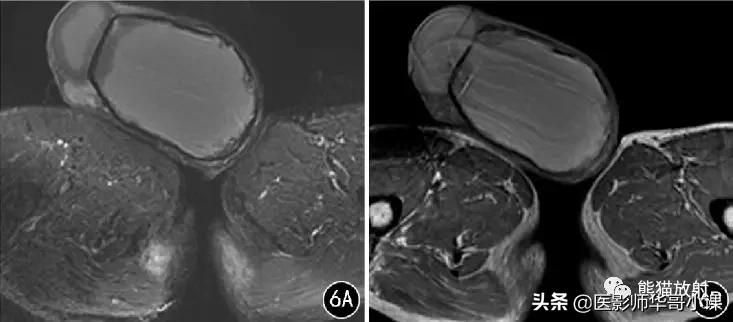

![[精品课件]畸胎瘤及精原细胞瘤(*丸睾**肿瘤及肿瘤样变CT及MR表现)](https://cdn.hadhvssabah.workers.dev/origin/pgc-image/363432124ff549eb8031031e872b3dfd.jpg)

图5 男,80岁, 双侧*丸睾**脓肿 。双侧*丸睾**肿大,信号不均,其内见液化坏死; 增强扫描可见明显环形强化,与附睾分界欠清,邻近皮肤增厚。